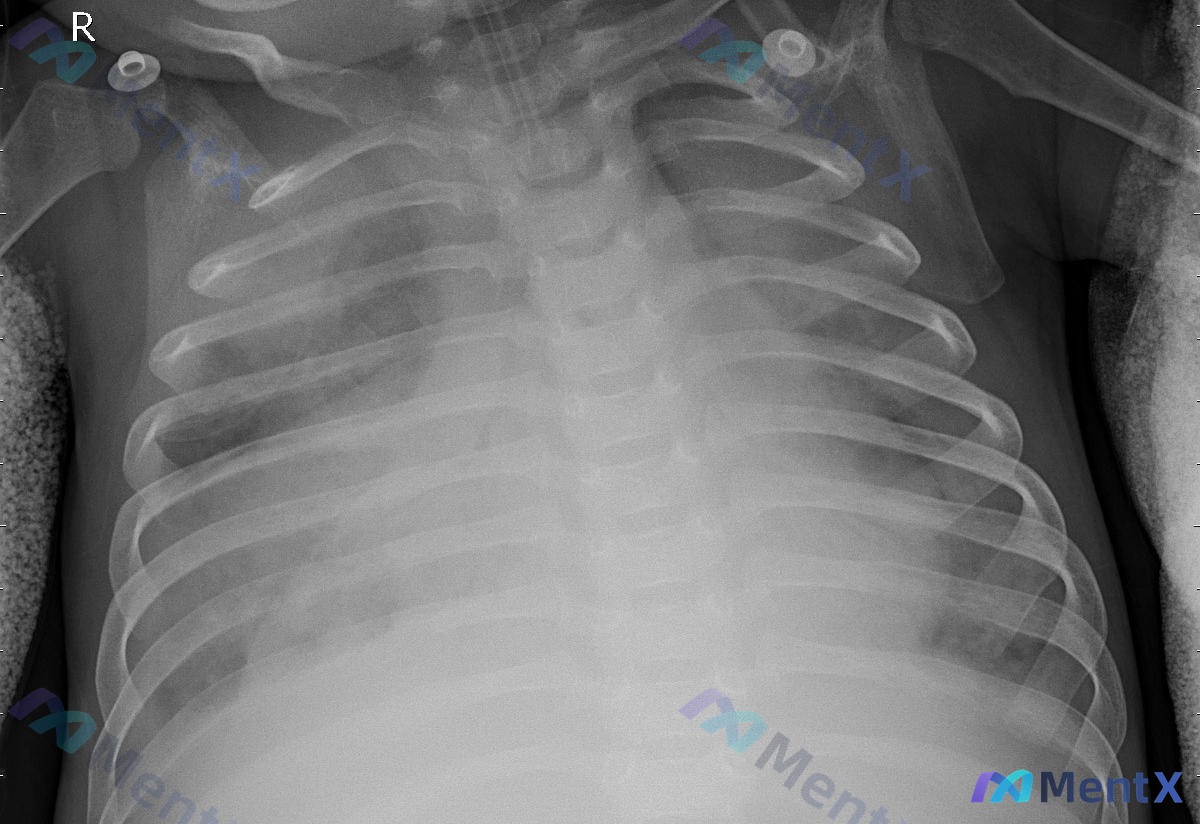

来一道5岁儿童的肺炎题,大家先看看: > 男,5 岁。剧烈咳嗽,咽痛,肌肉酸痛,咳淡红色痰,全身见多发红色皮疹,查体:WBC 8 × 10⁹/L,N 0.8。 > 考虑诊断是 > A. 支原体肺炎 > B. 金黄色葡萄球菌肺炎 > C. 链球菌肺炎 > D. 病毒性肺炎 > E. 肺癌 先不着急给答...

整理到一张儿科胸部正位X光片,先放客观影像表现,大家第一眼会怎么考虑? 基础情况:儿科,前后位(AP)投照 影像所见: - 气管居中,心影大小形态大致正常 - 双肺纹理增多、增粗、走行紊乱 - 双肺野(尤其右侧中下肺野及左侧中下肺野)可见散在模糊斑片状密度增高影 - 双侧肺门影稍显模糊,肋膈角清晰,...

整理了一份儿科胸部正位X光片的病例资料,影像表现和分析方向都比较有讨论价值: 基础影像背景: - 患儿是儿科人群,投照体位是仰卧位前后位(AP位) - 曝光适中,能看清肺纹理和纵隔结构 主要影像发现: 1. 双肺纹理增多、紊乱 2. 右肺野透亮度不均匀,可见多发斑片状、条索状模糊影,右肺门及肺中下野...

整理了一份小儿胸部正位X光片的读片分析资料,先放核心影像表现,不说结论,看看大家的第一反应: 基础信息: 儿科患者,胸部前后位(AP位)摄片 核心影像所见: 1. 双侧肺门区及肺纹理走行略显紊乱、增粗,以双侧中下肺野及肺门周围更明显 2. 双侧肺野可见弥漫分布的斑片状、条索状模糊影 3. 右中肺野及...

整理到一张幼儿的胸部正位X光片资料,先给大家放核心影像表现: > 投照体位对称,吸气度可; > 气管居中,纵隔见“帆影”(考虑幼儿胸腺),心影正常; > 双肺纹理增多、增粗、模糊,以肺门周围及中内带明显; > 双侧中下肺野见多发斑片状、云絮状高密度影,分布不均; > 肺门影稍模糊,肋膈角锐利,无积液...